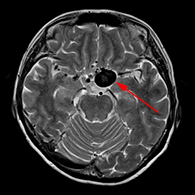

くも膜下出血の原因となる脳動脈瘤(のうどうみゃくりゅう)の外科治療

63歳女性、左眼視力低下で発症

<画像所見>

左眼の奥に大きな動脈瘤認める。

(→動脈瘤)